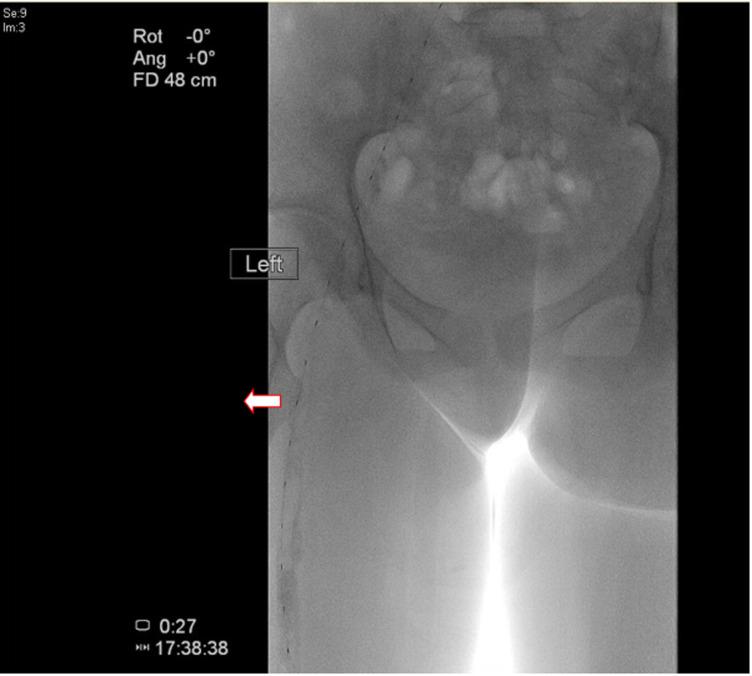

Deep vein thrombosis (DVT) in the pediatric population remains an infrequent yet clinically significant entity, with an estimated incidence of 0.07-0.14 per 10,000 children. We describe a unique case involving a previously healthy 16-year-old female who presented with progressively worsening left hip pain radiating to the knee, inability to weight bear, and associated limb heaviness with a purple discoloration on standing. Clinical evaluation revealed unilateral leg swelling, increased girth, and pain on passive joint movement, while initial radiographs were unremarkable; however, a markedly elevated D-dimer level prompted further investigation with Doppler ultrasound, which confirmed an extensive iliofemoral DVT. Owing to the lack of pediatric-specific guidelines, management was adapted from adult protocols, including thrombolytic therapy with tissue plasminogen activator and subsequent anticoagulation with dalteparin and apixaban, despite a complication of epistaxis that influenced the treatment course. This case highlights the diagnostic challenges inherent in pediatric DVT, highlights the necessity for a high index of suspicion when evaluating hip or leg pain in children, and emphasizes the urgent need for the development of dedicated pediatric guidelines to inform optimal therapeutic strategies.

儿童深静脉血栓形成(DVT)仍然是一种罕见但具有临床意义的病症,估计每10000名儿童中的发病率为0.07 - 0.14。我们描述了一个独特的病例,一名此前健康的16岁女性,出现左髋部疼痛逐渐加重并放射至膝盖,无法负重,站立时伴有肢体沉重感及紫色瘀斑。临床评估发现单侧腿部肿胀、周长增加以及被动关节活动时疼痛,而最初的X线片无明显异常;然而,D - 二聚体水平显著升高促使进一步进行多普勒超声检查,结果证实为广泛的髂股静脉DVT。由于缺乏针对儿童的指南,治疗方案参照成人方案,包括使用组织纤溶酶原激活剂进行溶栓治疗,随后使用达肝素和阿哌沙班进行抗凝治疗,尽管出现了鼻出血这一影响治疗进程的并发症。该病例凸显了儿童DVT固有的诊断挑战,强调在评估儿童髋部或腿部疼痛时高度怀疑的必要性,并强调迫切需要制定专门的儿童指南以指导最佳治疗策略。